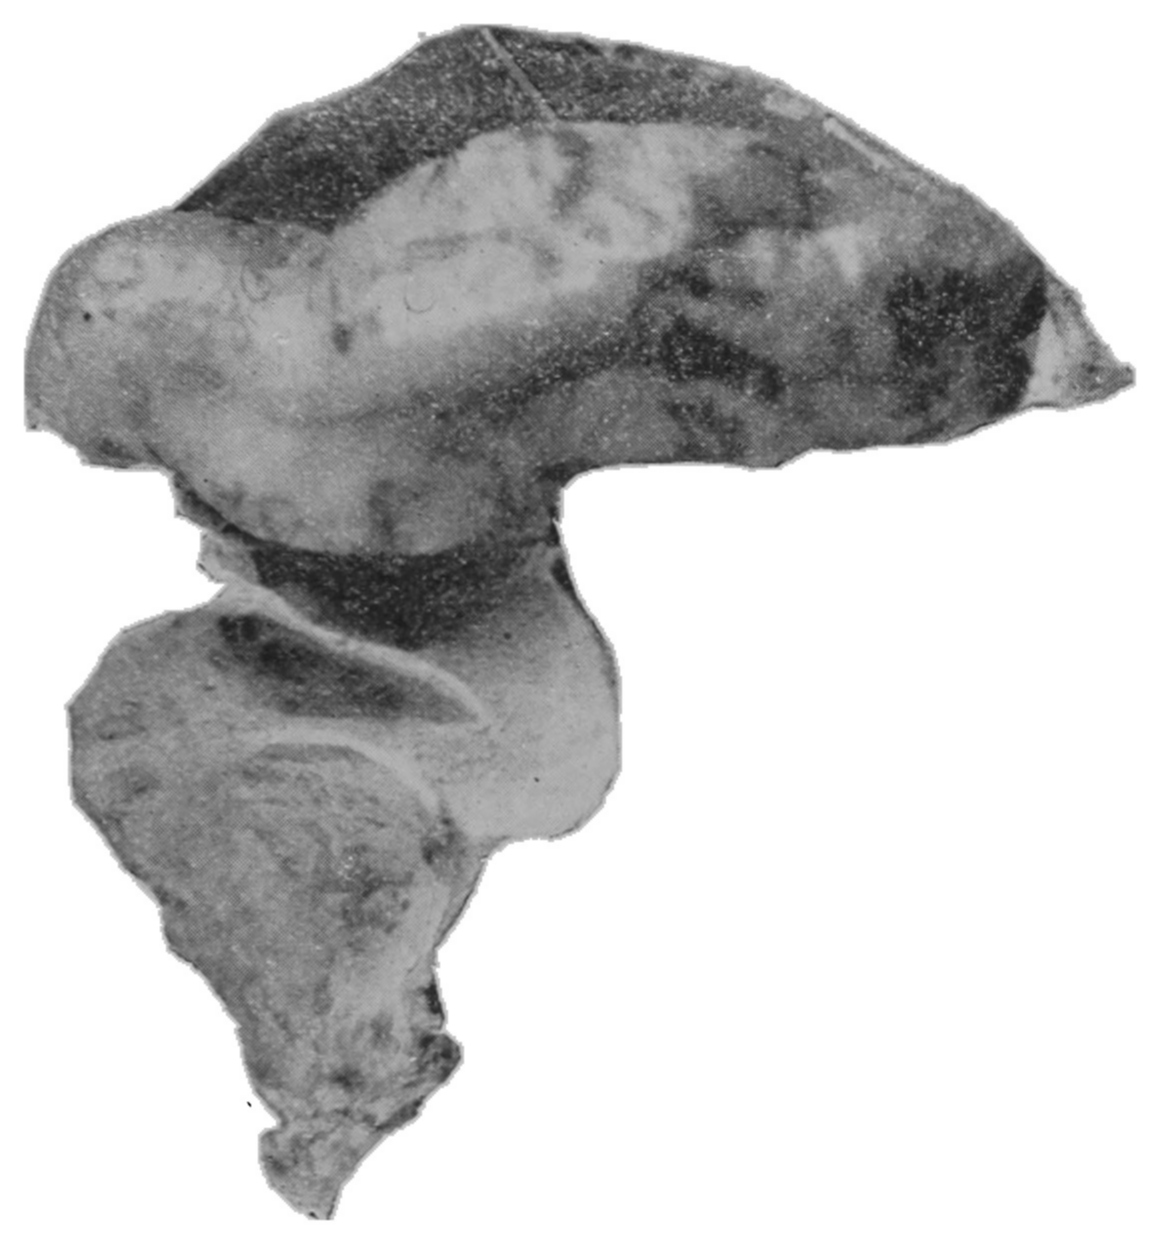

The photographic reproductions here published are documentary evidence of the existence of the obstructions under discussion. The sketch, Fig. 33, which was drawn from the valve while under the microscopic lens, exhibits the character of these obstructions and proves it that of a typic anatomic valve, and the absence of permanent bands of any other character in this organ is evidence that the semilunar valves and the so-called plica transversalis recti, Falten des Rectums, sphincter ani tertius, superior sphincter, and detrusor fecium muscles are one and the same thing and this thing is essentially a valve. It is most prominent when the gut is most distended.

The rectum may present to the eye of the imaginative observer the appearance of a chain of urinary bladders, communicating one with another by means of irregularly elliptic openings set at varying axes, and bounded by the nonparallel borders of the rectal valves. In the normal rectum the air-pressure smooths the mucous membrane evenly over the entire surface of the gut, as may be observed in the photographic illustrations. The normal mucous membrane of the so-called ampulla appears at first wet and of a shining bluish gray. As it dries, under the influence of gravitation the blue venous tint fades out of the gray and the wall assumes a pink tint.[39] Presently it acquires the appearance of parchment, and sometimes it appears painted at rare intervals with ramifying little arteries which may be crowded and overlapped by the larger companion veins; the latter are less arborescent and more suddenly dive and disappear in the bowel-wall. In time, over all there comes a sheen and the vascular pictures may fade away. These phenomena appear exactly as described only in the healthy rectum. In the diseased organ the color varies much.